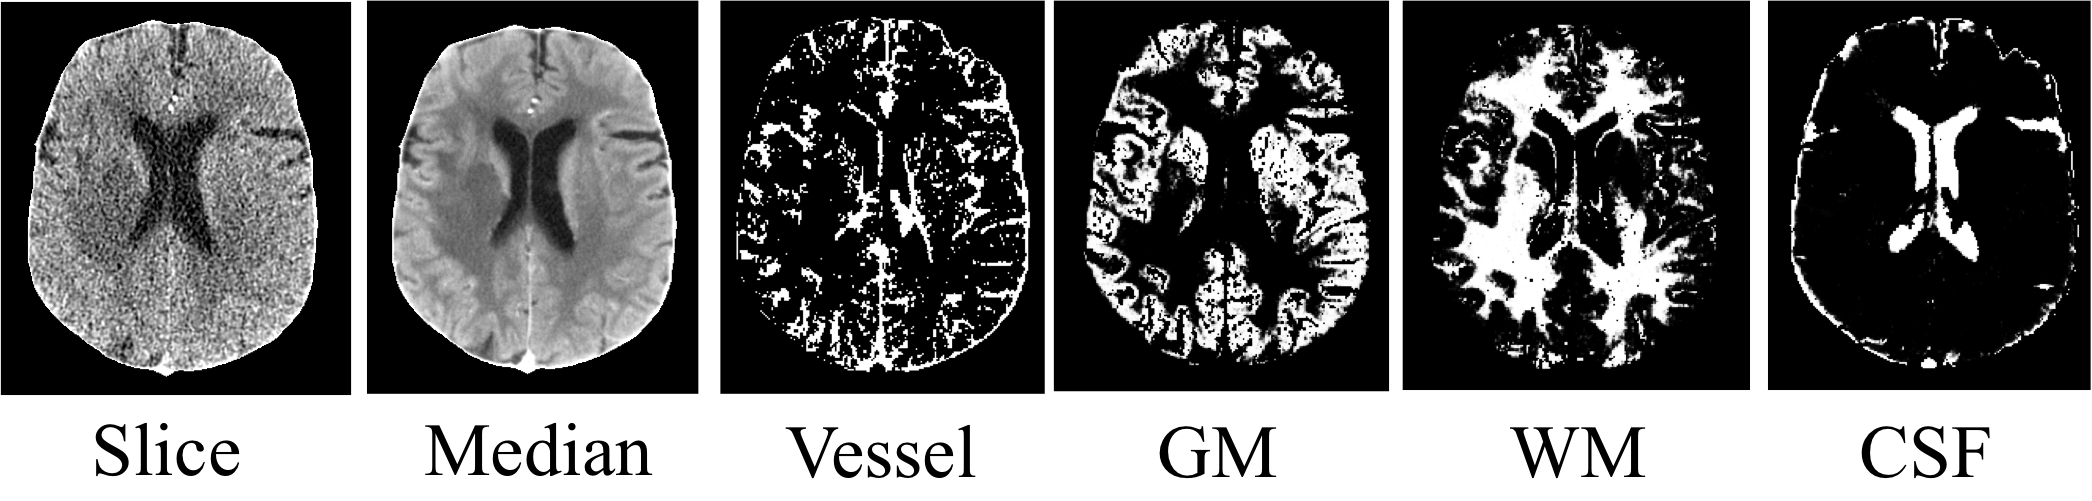

- STEP 1:Tissue Classification. Classify the voxels in CTP into four classes: vessel, gray matter (GM), white matter (WM) and cerebrospinal fluid (CSF).

Use Expectation-Maximization Segmentation (EMS) with contexture information incorporated by a MRF.

1. Learned dictionaries

Left is the global dictionary learned from all tissue classes. Right is the tissue-specific dictionary learned from white matter. The global dictionary is dominated by high-contrast, edge-like atoms, while the tissue-specific dictionary for WM has more low- contrast, fine structured atoms, as highlighted by red boxes.

Here we show the global dictionary (left) and the four tissue-specific dictionaries (right).